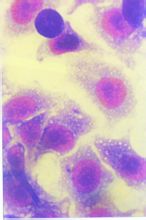

賈第蟲滋養體滋養體,一般指原生動物攝取營養階段,能活動、攝取養料、生長和繁殖,是寄生原蟲的寄生階段。在寄生蟲的原蟲中該階段通常與致病作用有關。在血鞭毛蟲中,無鞭毛體、前鞭毛體、上鞭毛體和錐鞭毛體以及剛地弓形蟲的速殖子和緩殖子都歸屬滋養體階段。痢疾內變形蟲的大小滋養體結構基本相同,但大小不同。大滋養體運動較為活躍,能分泌蛋白分解酶溶解腸壁組織。小滋養體運動較遲緩,寄生於腸腔,不侵蝕腸壁,以細菌和黴菌為食物。圓形或

橢圓形蟲體,內質顆粒小而均勻,含有染成藍黑色的紅細胞,細胞核1個,核膜內緣有一層排列整齊的染色質粒,核中央有一小而圓的核仁。滋養體有紫紅色的細胞核和藍色的細胞質,胞核為紫紅色,胞質為藍色.